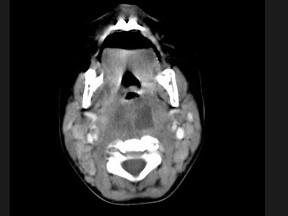

问题 10个月大的婴儿,发热,曾患中耳炎,CT扫描如图所示,请选择正确的描述或诊断 ( )

选项 A、考虑为咽后壁脓肿 B、考虑为咽后壁寒性脓肿 C、其内密度不均 D、颈椎骨质未见明显异常 E、咽后壁软组织肿胀

答案 ACDE